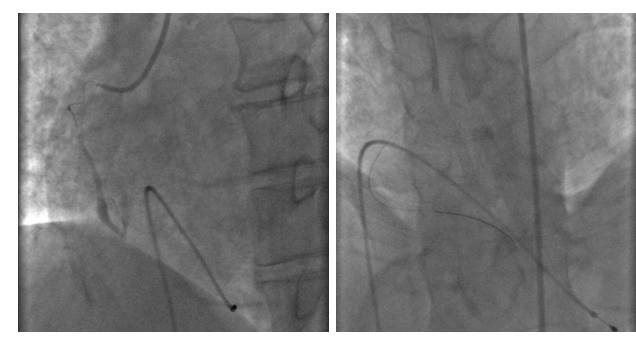

ECMO(急性心肌梗死 心源性休克)2016-12-4

2016-12-4ECMO+IABP+CRRT+呼吸机辅助通气

2016-12-6---拔除ECMO

12-20 冠脉造影+PCI术